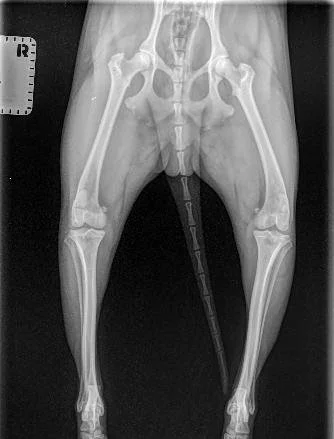

Cosmo’s cute little body from his X-ray

Cosmo had a blast and did an amazing job adapting to so many different environments. It makes me sad that we are now facing an up and coming knee surgery for him but grateful he injured himself while we were home and close to our vet than out of the country.

He is doing amazing on his pain medication but unfortunately with the severity of where his knee is it will require surgery to correct and help prevent future issues.